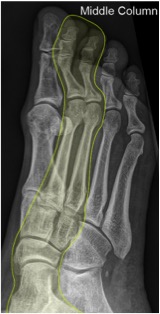

• Middle

• 2nd + 3rd metatarsals

• middle + lateral cuneiforms

• navicular

• talus

Lisfranc injury

• five critical radiographic signs that indicate presence of midfoot instability

• discontinuity of a line drawn from the medial base of the 2nd metatarsal to the medial side of the middle cuneiform

• seen on AP view

• diagnostic of Lisfranc injury

• medial side of the base of the 4th metatarsal does not line up with medial side of cuboid

• seen on oblique view

• disruption of the medial column line (line tangential to the medial aspect of the navicular and the medial cuneiform)